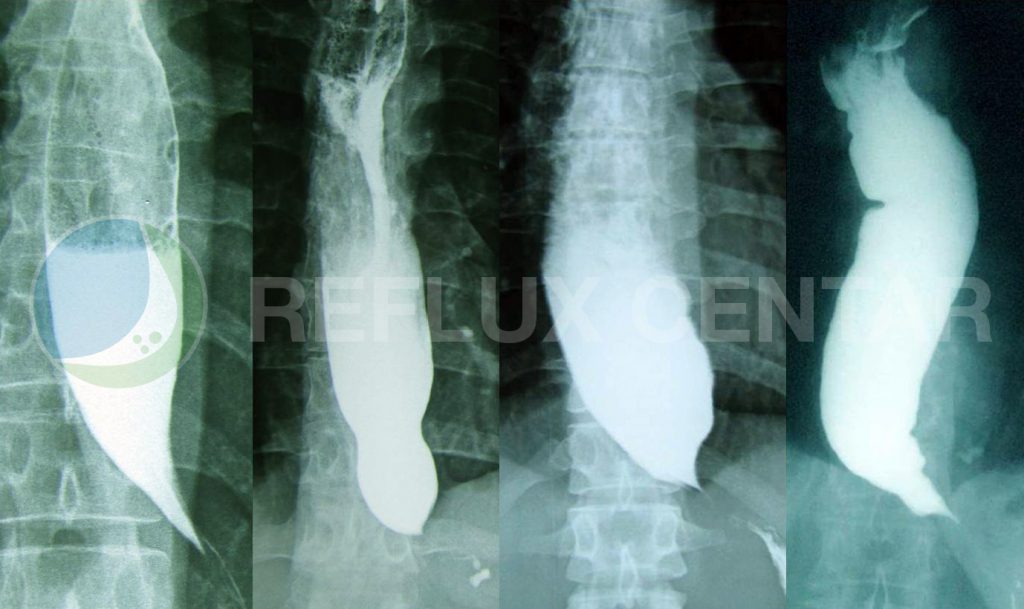

Kod pacijenata koji kao simptom imaju otežano gutanje (disfagiju), barijumaska radiografija je obično prvo dijagnostičko sredstvo koje se koristi u dijagnostici. Senzitivnost radiografije kod bolesnika sa ahalazijom je veoma visoka. Klasični nalaz na je postojanje tzv. „ptičijeg kljuna“ – suženja završnog jednjaka sa stubom kontrasta u lumenu jednjaka. Uočava se promenjiva dilatacija jednjaka, u rasponu od normalne odnosno blage (stadijum I incipijentna ahalazija) u ranim stadijumima, preko značajno proširenog (stadijum II dolihomegaezofagus) do masivno proširenog (stadijum III sigmoidni jednjak) jednjaka u završnoj fazi. Radiografskim ispitivanjem se mogu takođe videti nepropulzivne, tercijarne kontrakcije tela jednjaka sa nemogućnošću „čišćenja“ barijumskog bolusa iz distalnog jednjaka. Senzitivnost barijumskog ispitivanja je značajno viša nego kod endoskopije.